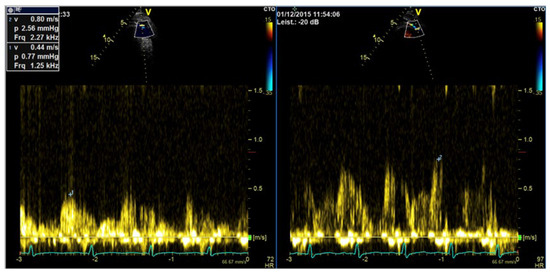

| Imaging method | CW Doppler for aortic stenosis/tricuspid regurgitation PW-Doppler: for pulmonary–venous flow |

| Imaging planes | Same as for non-contrast Doppler imaging, the enhanced color Doppler signals facilitate the alignment of the cursor for spectral Doppler measurements |

| Contrast application | Bolus injection, the recordings can be performed during the washout after recordings for assessment of LV function |

| Typical findings | Intensive Doppler spectra Consider reduction in gain or power. |